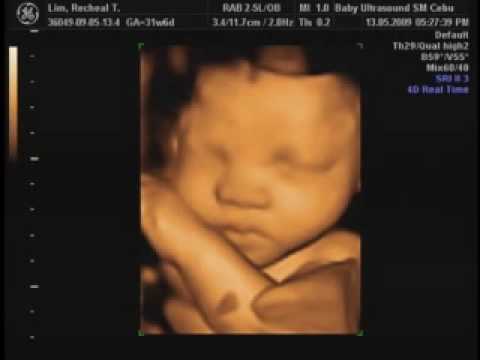

4D Ultrasound Taken On A GE Voluson E Baby Ultrasound Clinic ...

3D ultrasound 25 weeks, 4D view of baby, 25 week pregnancy, baby girl, first view - Duration: 14:46. Elena Elizabeth Wormington 1,186,919 views ... View Video

GE Medical Systems Ultrasound gemedical.com. RealTime 4D The new standard in women • 3D Multiplanar Display • 3D Power Voluson 730 PRO. RealTime 4D up to 16 volumes per second Next Generation of RealTime 4D Technology RealTime 4D imaging is the continuous, three-dimensional scanning ... Get Document